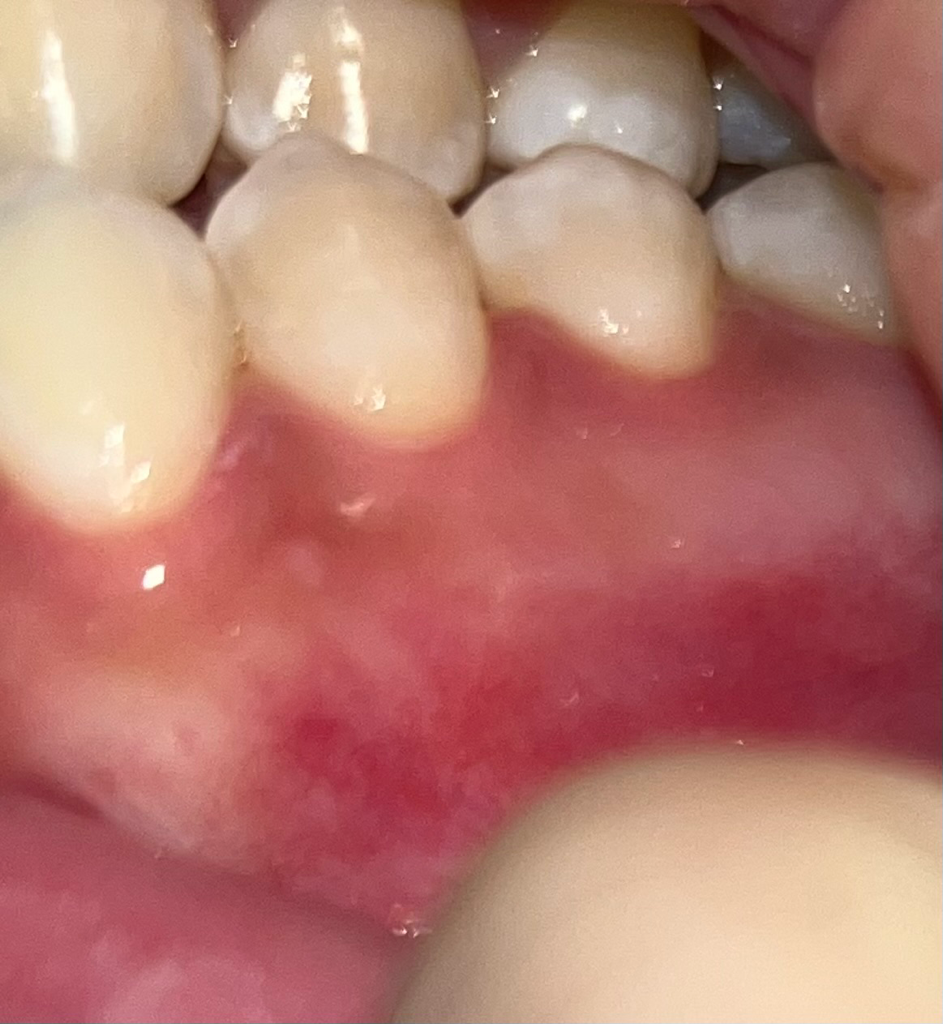

잇몸 색이 살짝 갈색이에요 ㅜ ㅜ

밑부분 살짝 어두운거 약간 색변한거 보이시나요 ?̊̈ ㅜㅜ 흡연때문일까요 ?̊̈ 이부분만 그래요,, ㅜㅜ 문제있는걸까요.. ?̊̈ ㅜㅜㅠㅠ(⸝⸝⸝ᵒ̴̶̷̥́ ⌑ ᵒ̴̶̷̣̥̀⸝⸝⸝)

잇몸이 검게 보이는 경우 흡연자의 경우 니코틴 및 타르색소가 침착되어 나타날수 있습니다. 잇몸질환예방을 위해 스케일링을 받고 현재 상태를 확인해보길 권합니다.

1. 흡연자이시면 흡연으로 인해 잇몸건강에 영향을 분명 받습니다.

2. 그 외에도 잇몸에 염증이 있는 상태에서 잇몸질환이 유발된 경우 위와 같이 잇몸 색이 정상(선홍색)에서 변할 수 있습니다